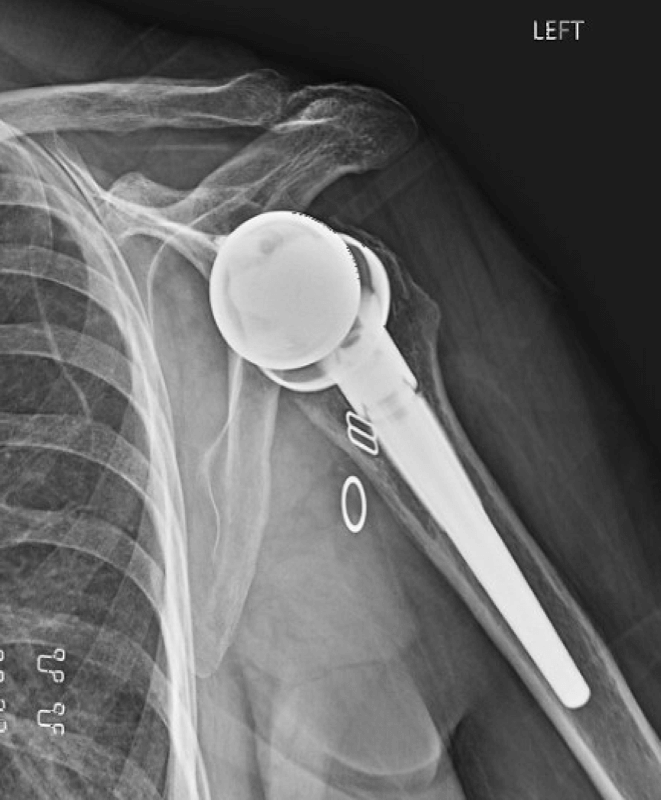

Lima, Augmented